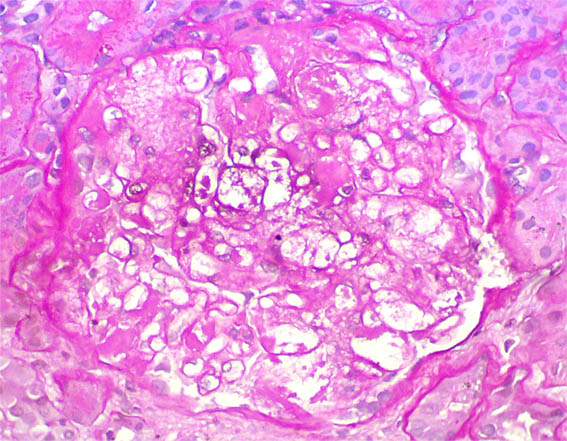

Figure 3. H&E, X400.

Figure 5. PAS stain, X400.